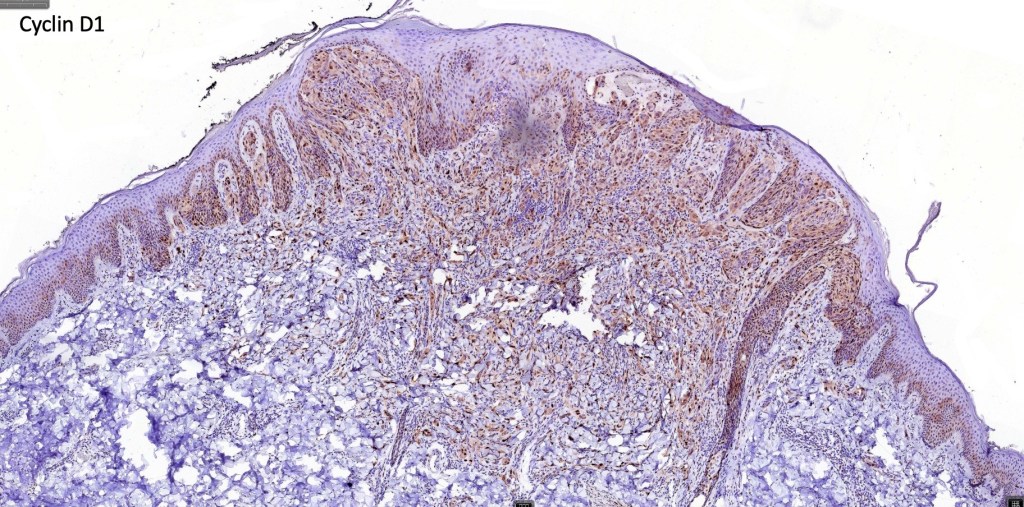

•S100, MART1 & SOX10 +ve, HMB45 +ve (superficially & lost progressively with depth), p16 +ve, p21 +ve